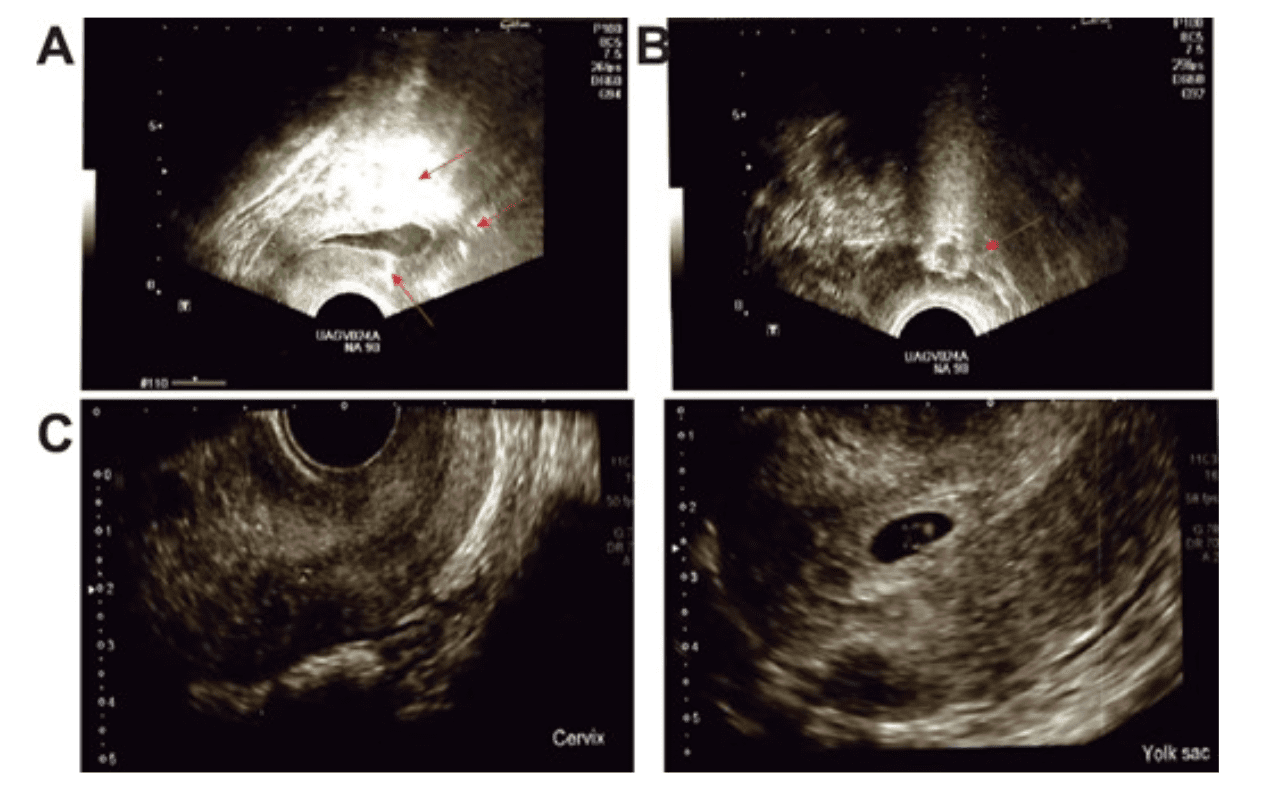

This figure shows that, after intrauterine infusion of autologous PRP, endometrial thickness increased significantly compared to before treatment. Panel A shows the overall change; panel B shows that this improvement occurred both in normal-weight patients and in overweight or obese patients; and panels D and E show that even in women who achieved implantation or successful pregnancy, the endometrium was also thicker after the procedure. In simple terms, this image supports that the treatment helped the uterus become more prepared to receive the embryo.